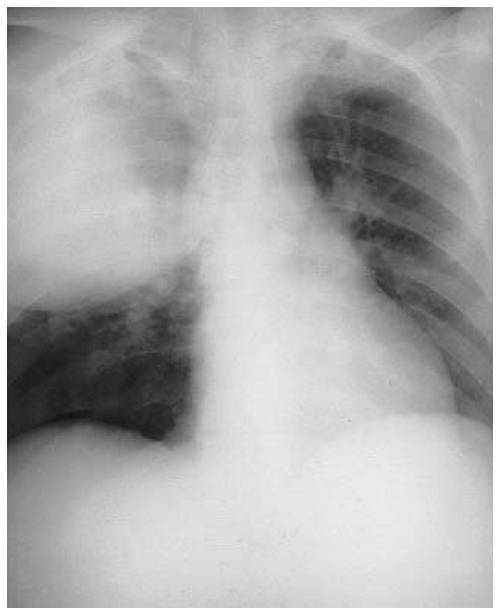

Диагностировать заболевание можно с помощью рентгенографии или компьютерной томографии грудной клетки (показывают инфильтраты (уплотнения) в легочной ткани), биотического анализа крови, общего анализа крови, анализа крови на газы, бактериологического посева мокроты.